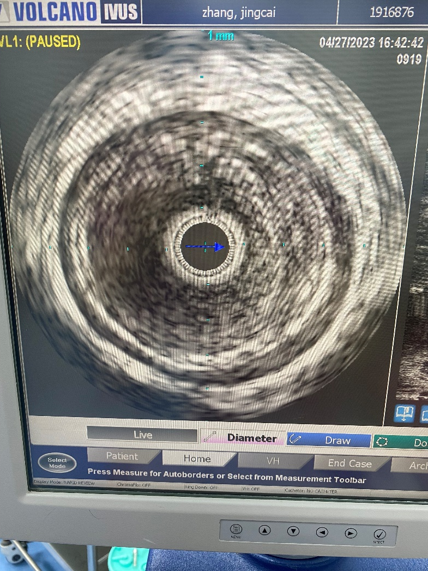

确认导丝位置

在CTO病变开通过程中,导丝可能位于真腔、内膜下甚至中膜层。DSA有时难以准确判断。IVUS可以明确导丝的位置,这对于后续治疗策略有决定性影响。若导丝位于内膜下,贸然使用Rotarex等减容装置可能引发血管穿孔等严重并发症。而确认真腔通过后,方可安全进行后续操作。

病例1(股腘动脉CTO):

一例重度间歇性跛行患者,导丝通过股腘动脉CTO病变后,若仅凭DSA判断,可能直接进行Rotarex减容。但IVUS检查发现导丝实际位于内膜下(假腔)。此时若进行减容,风险极高。术者遂调整策略,改用球囊扩张后植入Viabahn支架,成功避免了严重并发症。